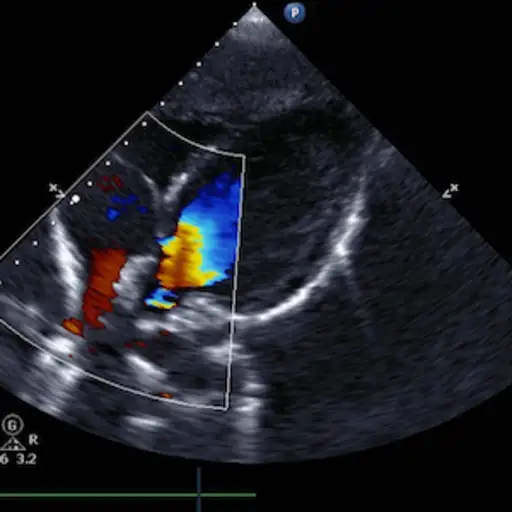

这些是诊断淋巴瘤最常用的检查方法。如果病人有骨痛,有时需要做骨扫描。和超声心动图,多门控采集(MUGA)扫描对于那些需要化疗且有心脏或肺部疾病风险的患者,通常要求进行肺功能测试。